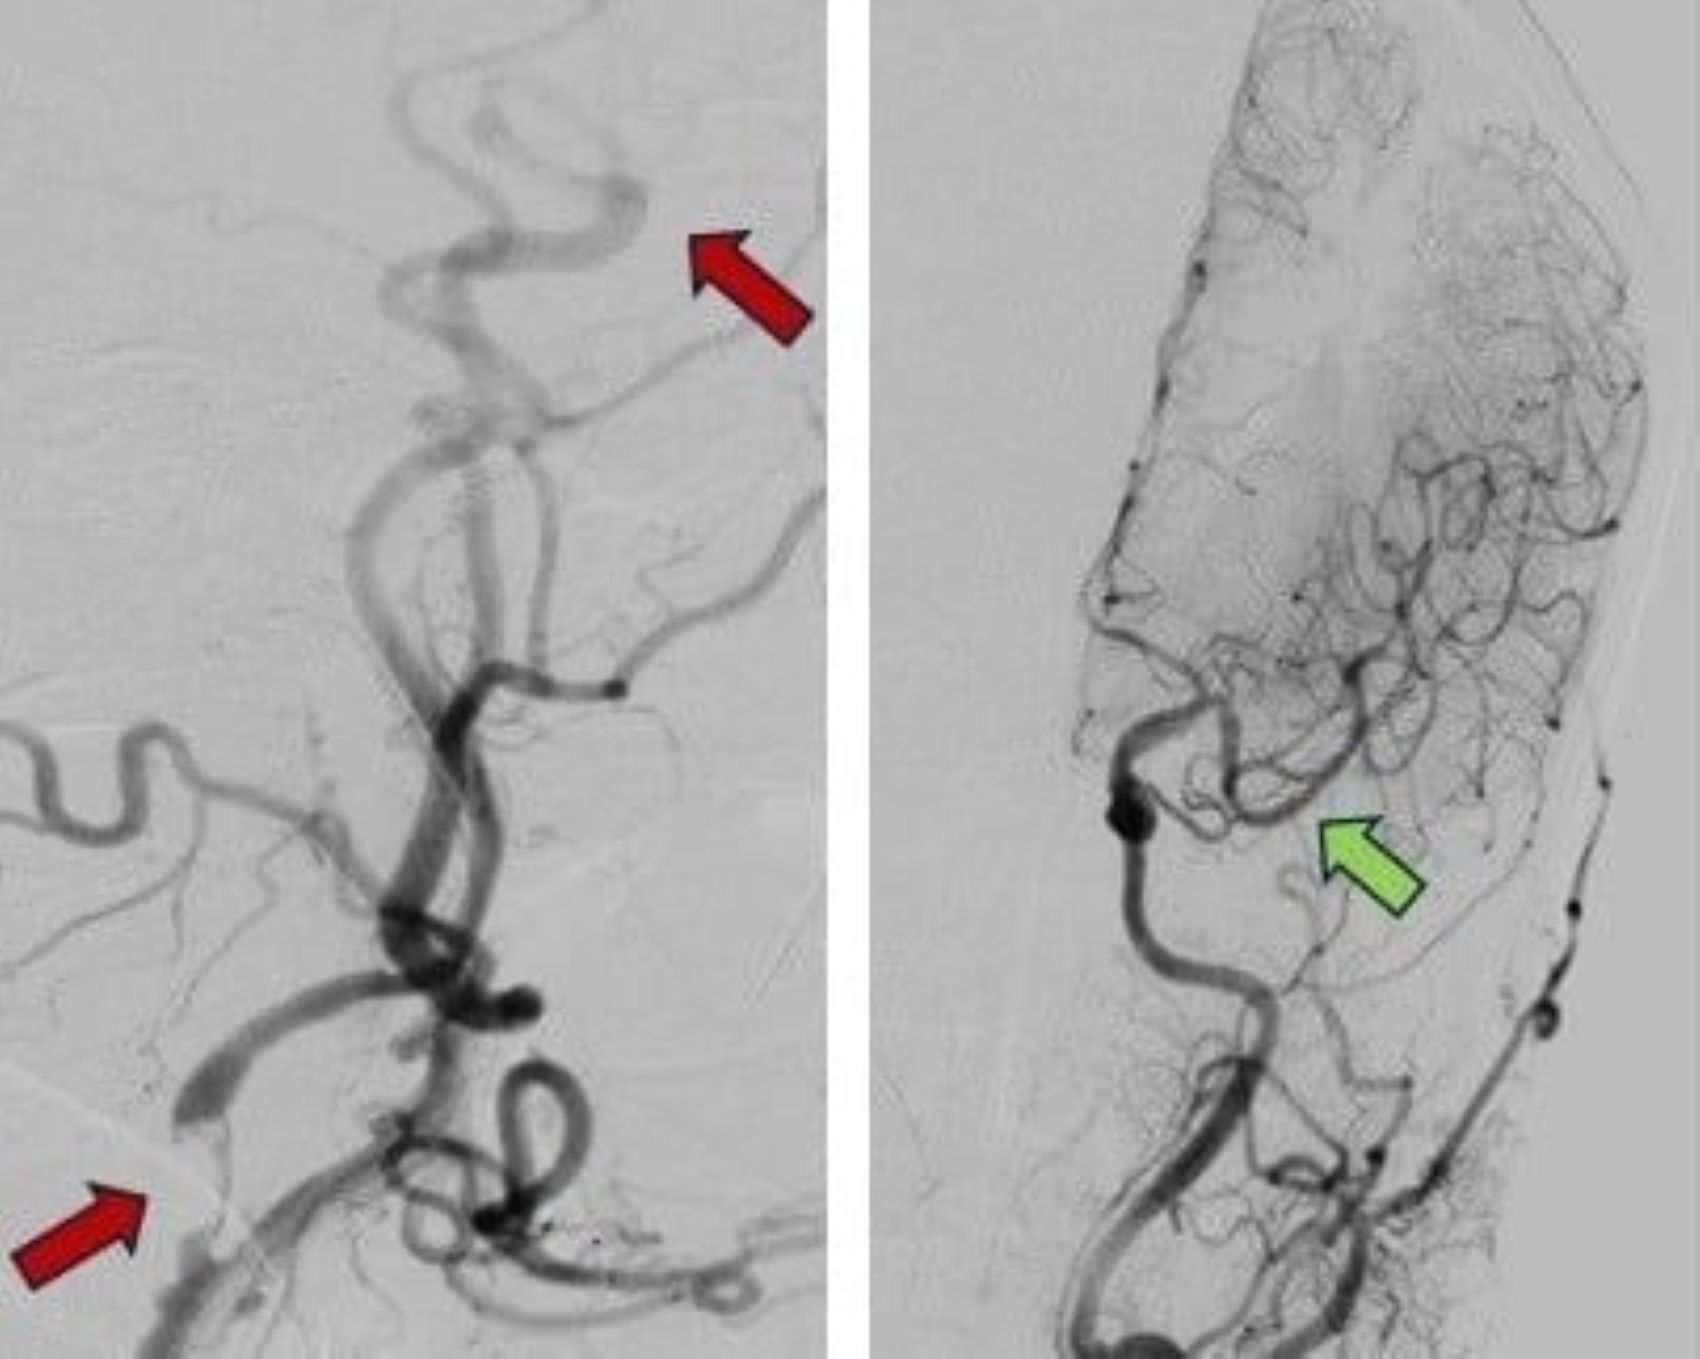

수막구균 감염 사례 증가, 의사 위험한 합병증 경고

앞으로 수막구균성 뇌수막염이 계속 발생하여 국민 건강에 영향을 미칠 위험이 있습니다.